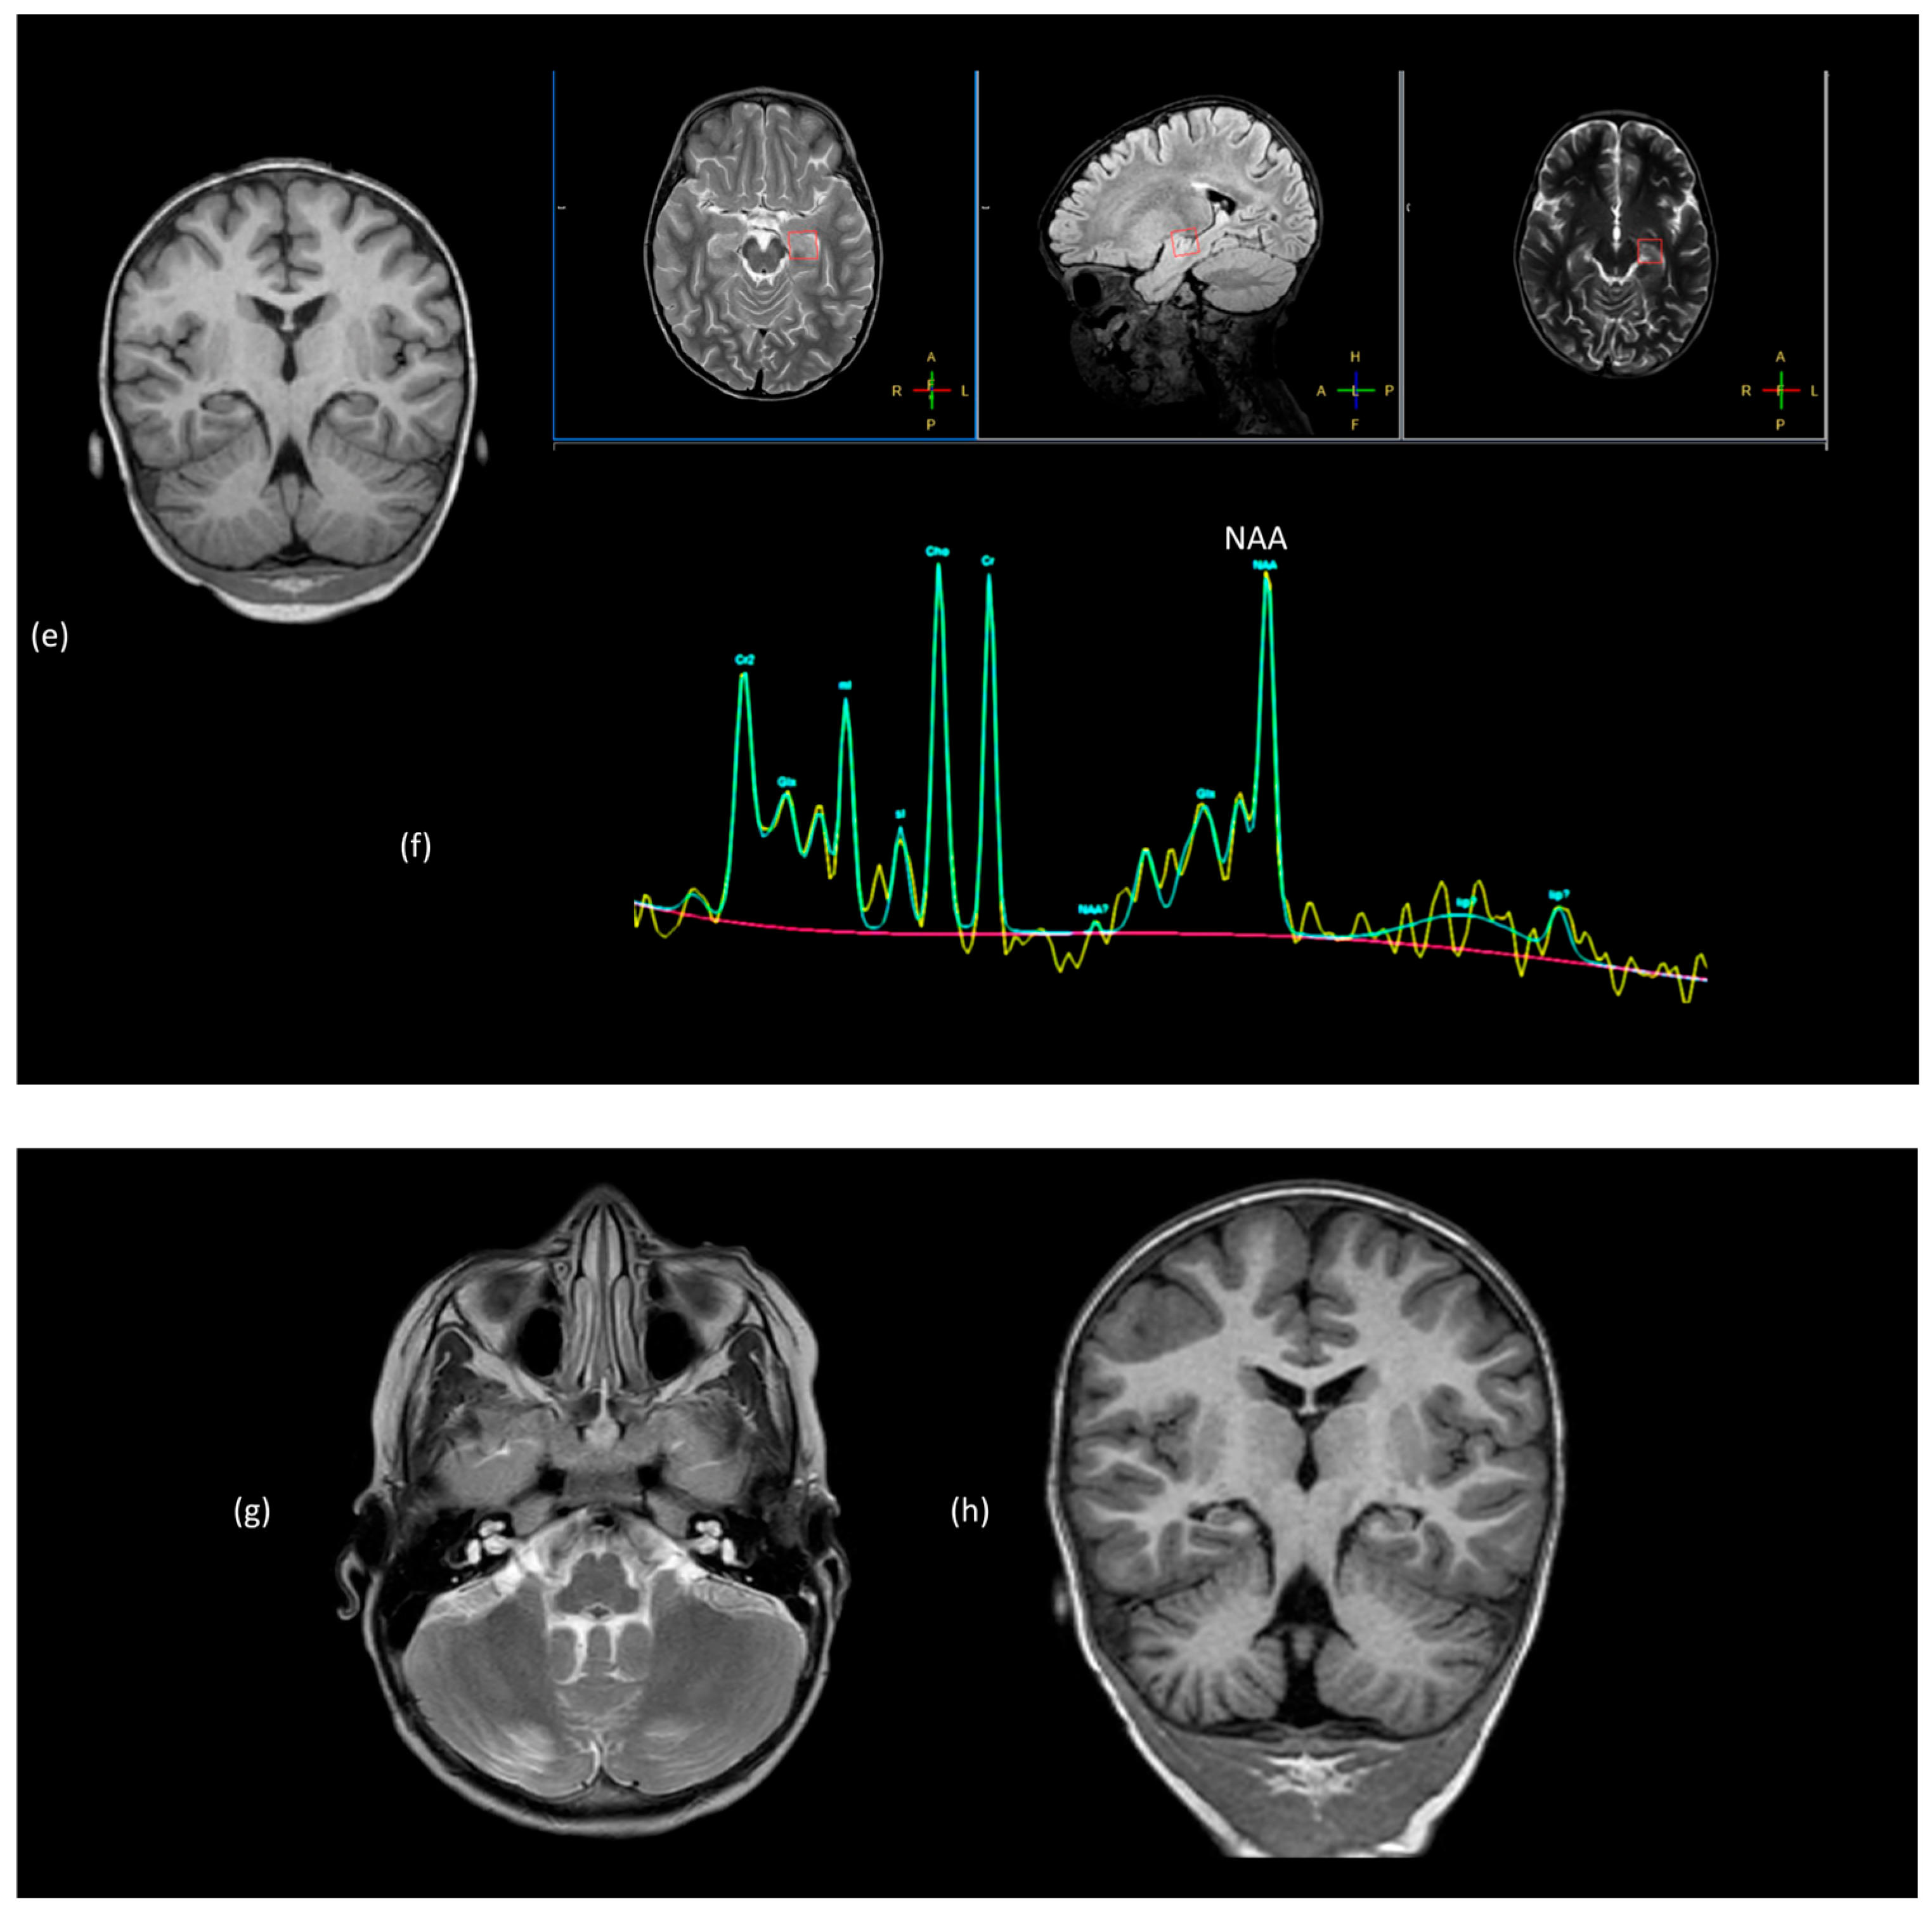

1. Introduction

2. Multiple Sclerosis

2.2. Conventional Neuroimaging

2.3. Advanced MRI Techniques

2.4. Summary of Imaging in Pediatric Patients with POMS